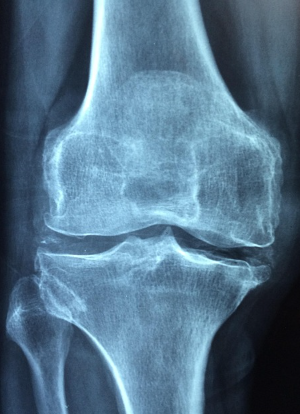

첫째, 관절 주변 근육을 강화하는 근력 운동이 필요합니다. 근육이 약하면 관절이 직접 하중을 받아 손상될 가능성이 커집니다. 예를 들어 무릎 관절을 보호하려면 대퇴사두근, 햄스트링, 둔근을 균형 있게 발달시켜야 합니다.

셋째, 과학적으로 입증된 ‘저충격 운동(Low Impact Exercise)’을 실천해야 합니다. 점프나 무거운 중량을 드는 운동은 관절에 급격한 압력을 가해 손상을 유발할 수 있으므로, 체중 부하가 적고 안정적인 동작을 선택하는 것이 좋습니다.